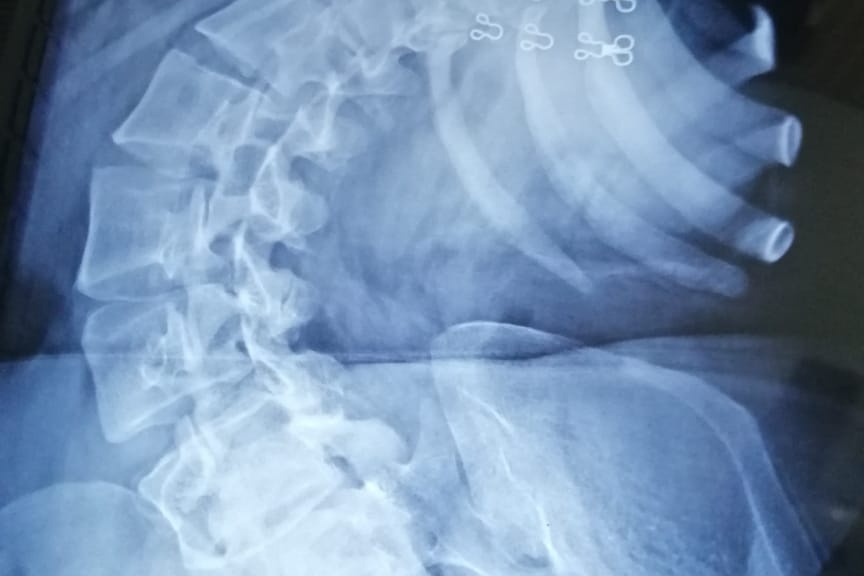

I went to an orthopedic in Islamabad. Only an X-ray determined the nature of my spinal curve. He recommended MRI's for further diagnosis. These MRI's cleared that my kidneys have been deformed and my lungs and heart are under great compression. This situation could be life threatening to me. For the pain management he prescribed me heavy pain killers which I have to take 3 times a day. My kidneys are getting badly affected from this medication. I am also unable to got out or socialize due to this pain, so this thing is causing me depression as well. My respiratory system is also under a lot of compression due to my curved spine which causes shortness of breath.

For the meantime those pain killers helped me to get rid of this pain and I started working as a freelancer to support myself financially. Things were better until I started experiencing a severe pain & fatigue again due to long sitting hours. My curve got even worse with the cob angle of 100+ degrees and I left the job. This state of affairs effectively means that my life has come to a standstill.